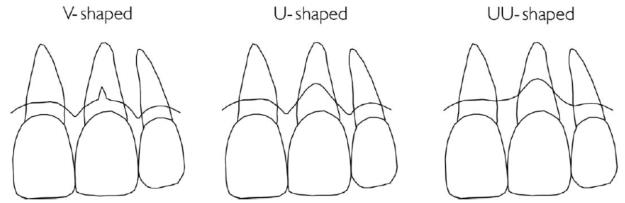

- 唇側dehiscence

- V-shape:

- 只有在牙根最中、前側有小缺損(僅侷限在middle third)

- Growing potential:容易生長,主要依靠兩側的骨頭

- U-shape:

- 比較大,但侷限於牙根最distal與最mesial的範圍內

- Growing potential:主要靠兩側的interdental bone主導

- UU-shape:

- 超過牙根範圍,涉及interdental bone的程度(或碰到鄰牙)

- Growing potential:很差,牙根表面很難長骨頭,做即拔即種的話,此種成品最不美觀

- V-shape: